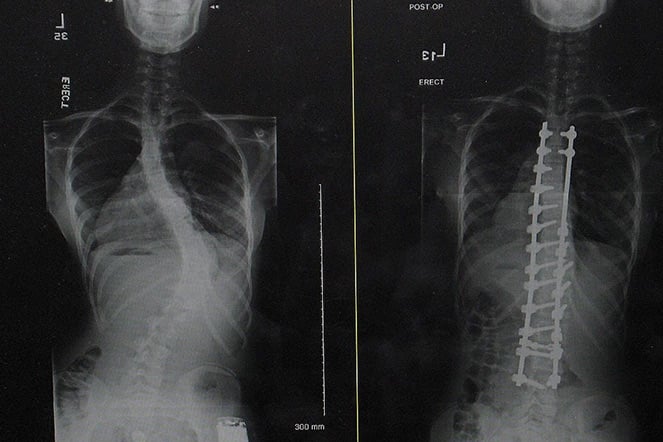

X-rays from before and after surgery.

Elliana was diagnosed with scoliosis right before she turned 11. It was a difficult couple of years because the progression of the scoliosis was becoming more and more difficult to manage.

When the Iowa native was referred to Shriners Children's St. Louis, she and her family were expecting to hear she might need surgery several years down the road. Instead, the world-class team decided she needed to have surgery as soon as possible.

“That was a big pill to swallow, as a 12- to-13-year-old,” she said. “We ended up scheduling the surgery about six months after I had that first appointment.”

Following a host of preoperative visits, the five days at the hospital the week of the surgery was a little bit of a blur. However, the overall experience remains galvanized in her mind more than a decade later.

“I think what always stuck out to me was the friendly environment. It was never scary and I never felt just shuffled in and out,” she said. “The medical treatment I received at Shriners enabled me to live life to the fullest. Getting that treatment enabled me to do a lot of things that I probably wouldn't have been able to do had I not had the surgery. Plus, experiencing the medical side of things at such a young age really did pique my curiosity and gave me a passion to pursue a career in the medical sciences.”